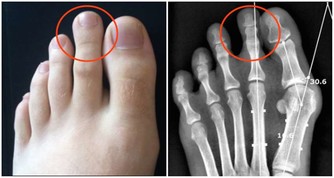

在我們爬山、爬樓梯的過程中,軟骨承受的壓力增加,

每上一級樓梯膝關節軟骨面將承受超過體重4倍的壓力,跑步時就更大了。

另外,爬樓梯或爬山時膝蓋除了承重增加,還要前後移動、側向扭轉,

尤其膝關節前端的髕骨部位承受壓力最大,對半月板等關節軟組織也會造成磨損。